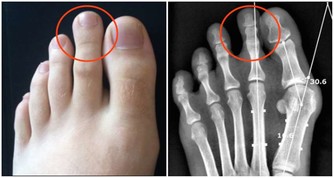

4、按摩的地方沒有感染、嚴重的皮膚病,如各種急性傳染病,急性骨髓炎,結核性關節炎,傳染性皮膚病,皮膚濕疹,水火燙傷,皮膚潰瘍,腫瘤,以及各種瘡瘍等。